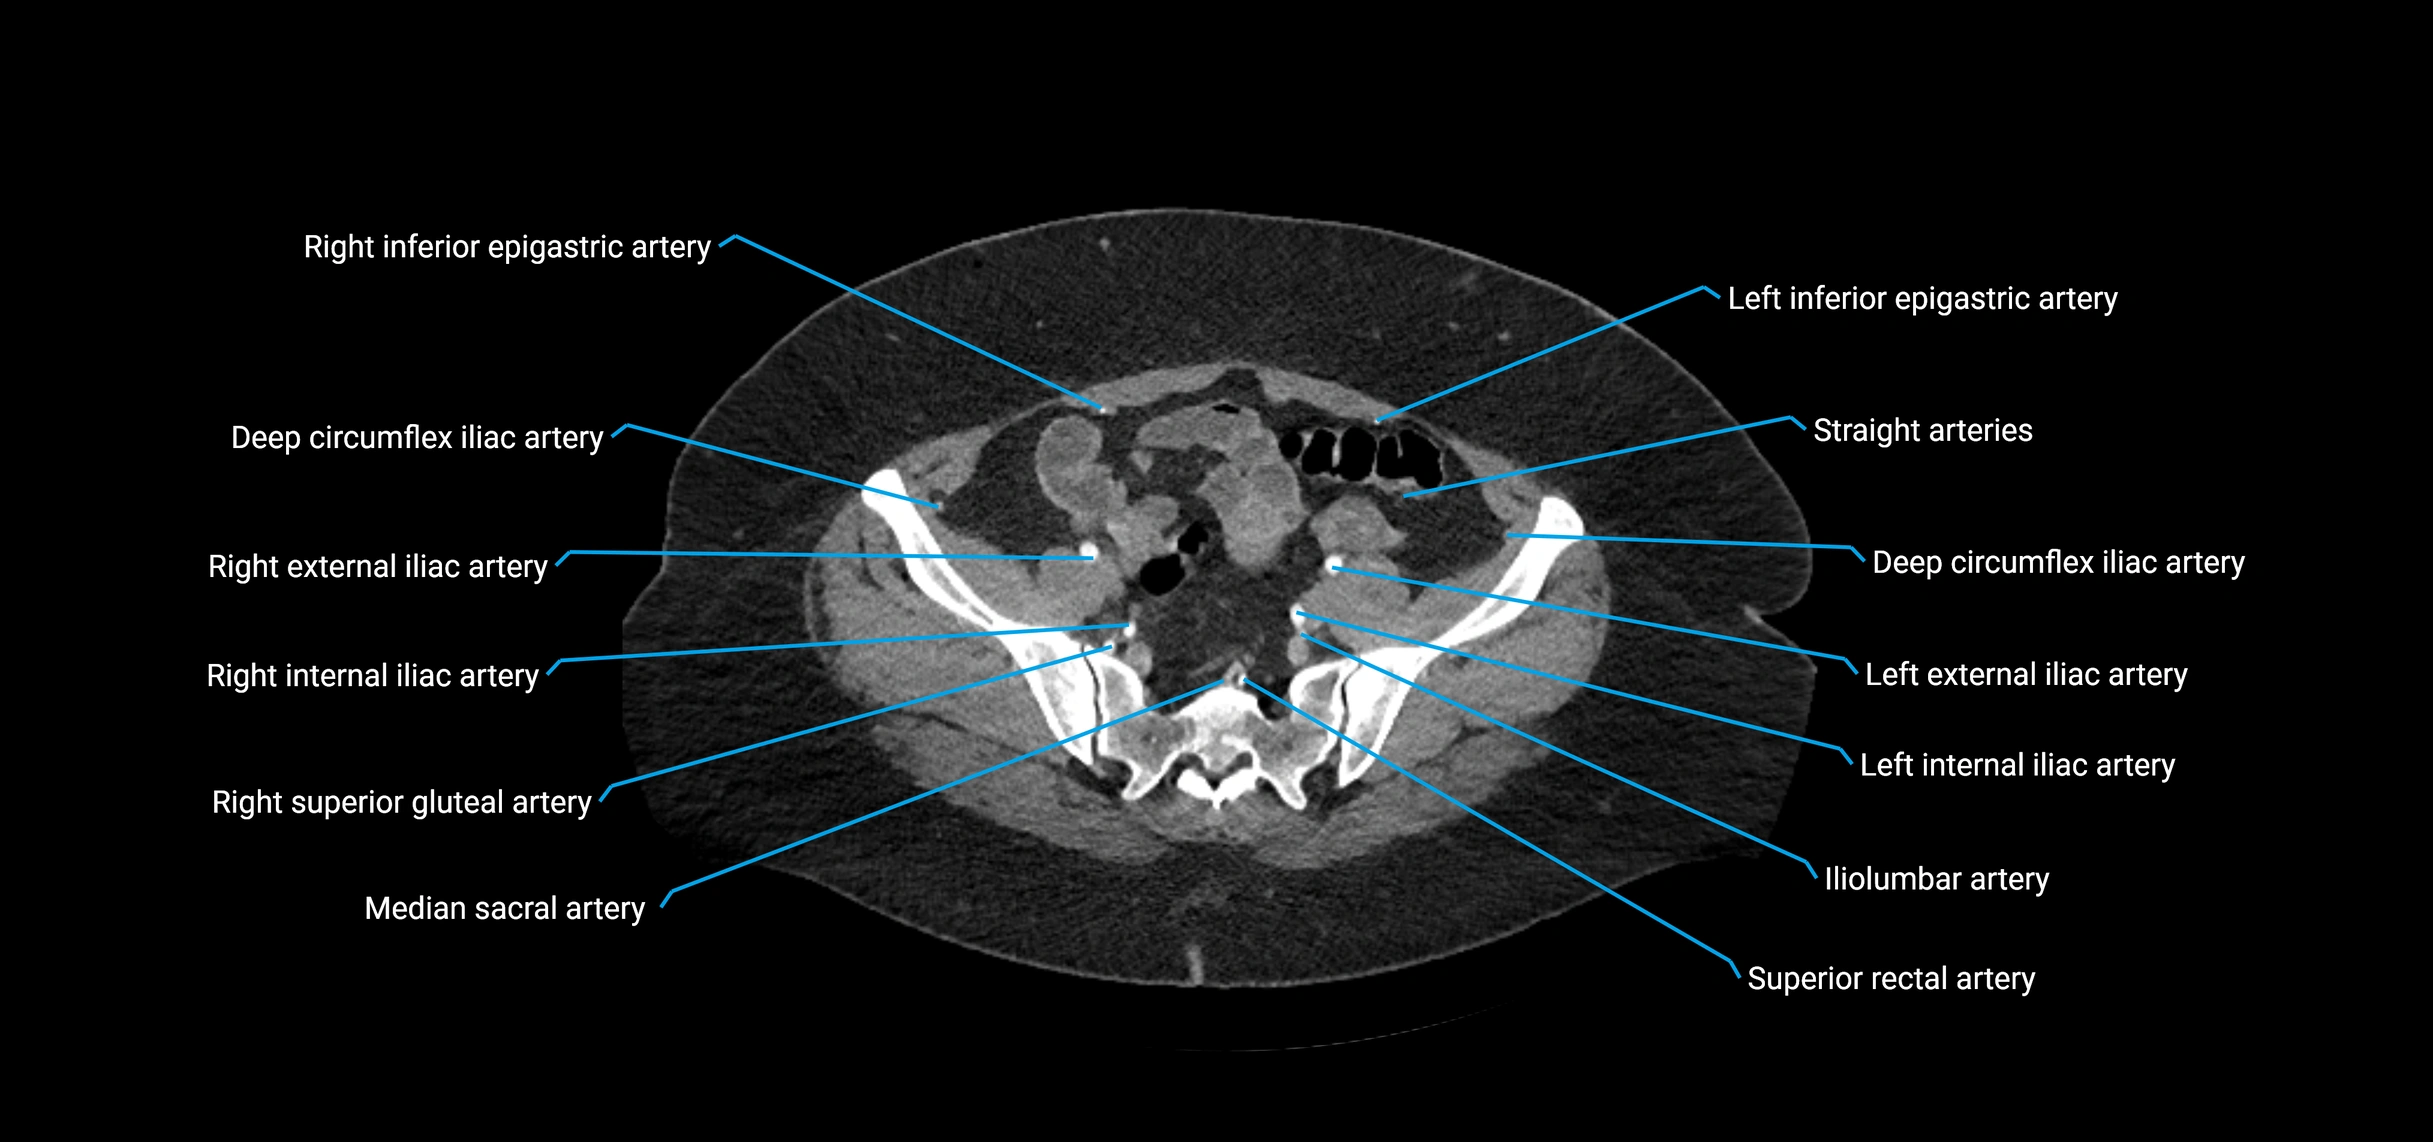

CT images

image